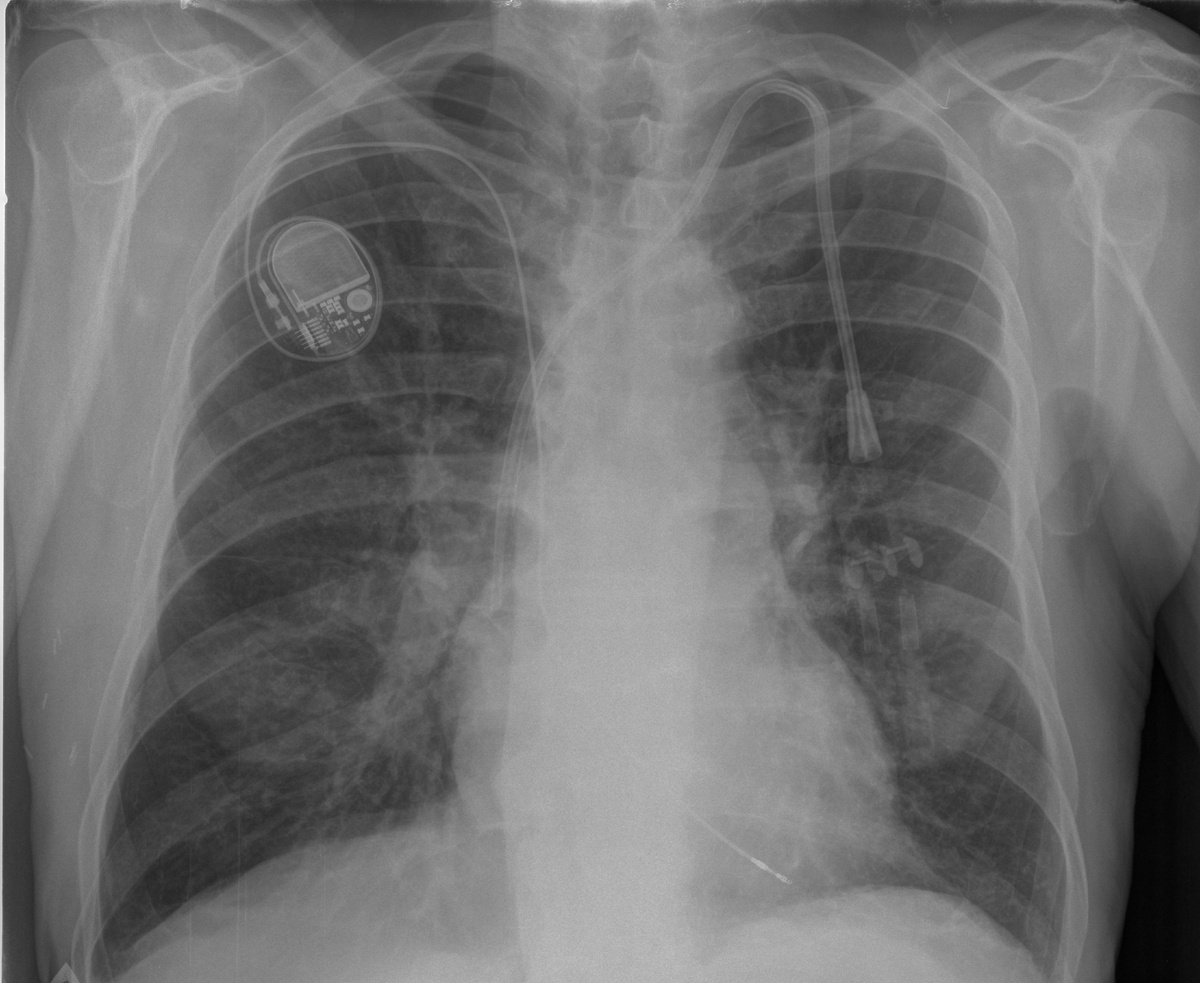

На рентгеновских снимках ЦВК визуализируются как тонкие линейные структуры, которые могут проходить от места введения (например, яремной или подключичной вены) до правого предсердия, где они должны правильно размещаться для обеспечения оптимального функционирования. Ключевыми аспектами, на которые врачи обращают внимание при интерпретации рентгенограмм, являются:

1. Положение катетера: Идеальное расположение ЦВК синдрома осуществляется вблизи передней стенки правого предсердия. Рентгенограмма позволяет врачу убедиться, что кончик катетера находится в правильной области, что минимизирует риск тромбообразования и травмирования сосудов.

2. Оценка состояния сосудов: Рентгеновские снимки также используются для визуализации вен, в которые вводился катетер. Наличие признаков разрывов, тромбообразования или других изменений может быть замечено на этих изображениях. Это позволяет врачам принимать решения о необходимости дальнейшей терапии или вмешательства.

4. Дополнительные технологии визуализации: С развитием медицинских технологий рентгенография с контрастными веществами, компьютерная томография (КТ) и магнитно-резонансная томография (МРТ) становятся все более распространенными методами для проверки расположения и состояния центральных венозных катетеров. Эти методы могут дать более детальную информацию о взаимодействии катетера с окружающими тканями и сосудами.